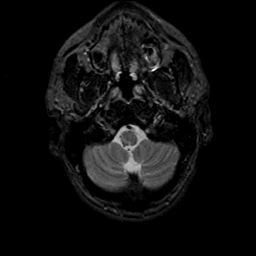

MR Study #9, April 14, 1991 -- Slice #5

[Home][Help][Clinical][Tour 1][Tour 2] Slice 5